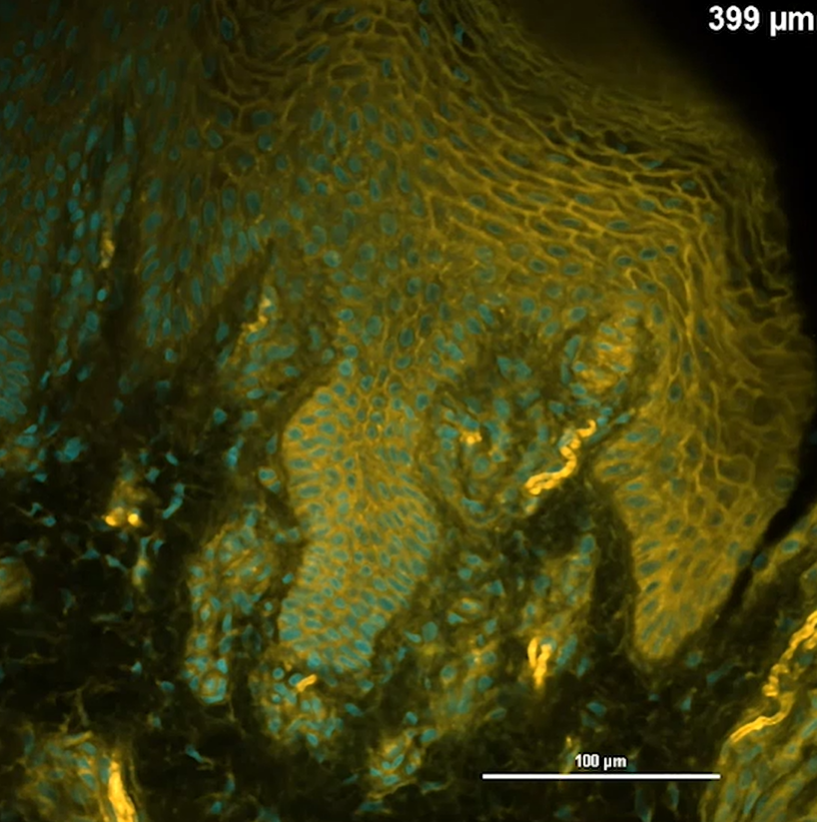

使用双光子激光显微镜对透明化人正常皮肤组织进行成像

使用4% para-formaldehyde/ PBS固定人正常皮肤组织块后,制备成500 μm的切片,同时进行76 h的组织透明化处理(LUCID)和HistoBright(10 μM)染色。通过双光子激光显微镜,用960 nm处激光激发组织块,分别在492 nm(SHG:青色)、500-550 nm(绿色)、560~593nm(橙色)和 593-690 nm(红色)处分别获取荧光图像,制作以下4幅合成图像。

※ 492 nm(青色)来源于组织中胶原纤维的SHG信号,而非HistoBright来源的荧光信号。

接下来,使用双光子激光显微镜在Z轴方向以5 μm的间隔连续拍摄500 μm的图像,并使用图像分析软件进行三维构建,以三维方式将人皮肤组织的精细结构可视化。